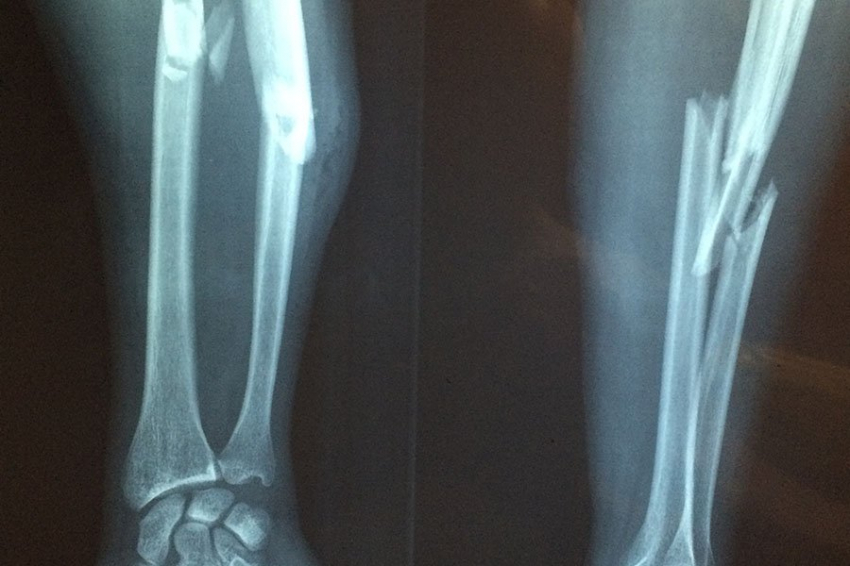

Во Владикавказе прошла школа по профилактике падений и переломов

Во Владикавказе состоялась школа по внедрению комплекса мер, направленного на профилактику падений и переломов у лиц пожилого и старческого возраста (Комплекс мер) в рамках реализации федерального проекта «Старшее поколение» национального проекта «Демография».

В программе школы были освещены основные вопросы профилактики падений и переломов, а также организации и внедрения комплекса мер, направленных на улучшение текущей практики оказания медицинской помощи пациентам старше 60 лет.

Программа профилактики падений и переломов внедряется во всех регионах страны, в том числе в Республике Северная Осетия-Алания. Участники мероприятия обсудили, что необходимо выявлять пациентов с риском переломов, оценивать эти риски и формировать группы, требующие особого внимания.

«Остеопороз – одно из наиболее распространенных заболеваний костно-мышечной системы среди лиц пожилого возраста, приводящее к снижению прочности кости.», – отметила Наталья Торопцова, заведующая лабораторией остеопороза НИИ Ревматологии им. В.А. Насоновой.